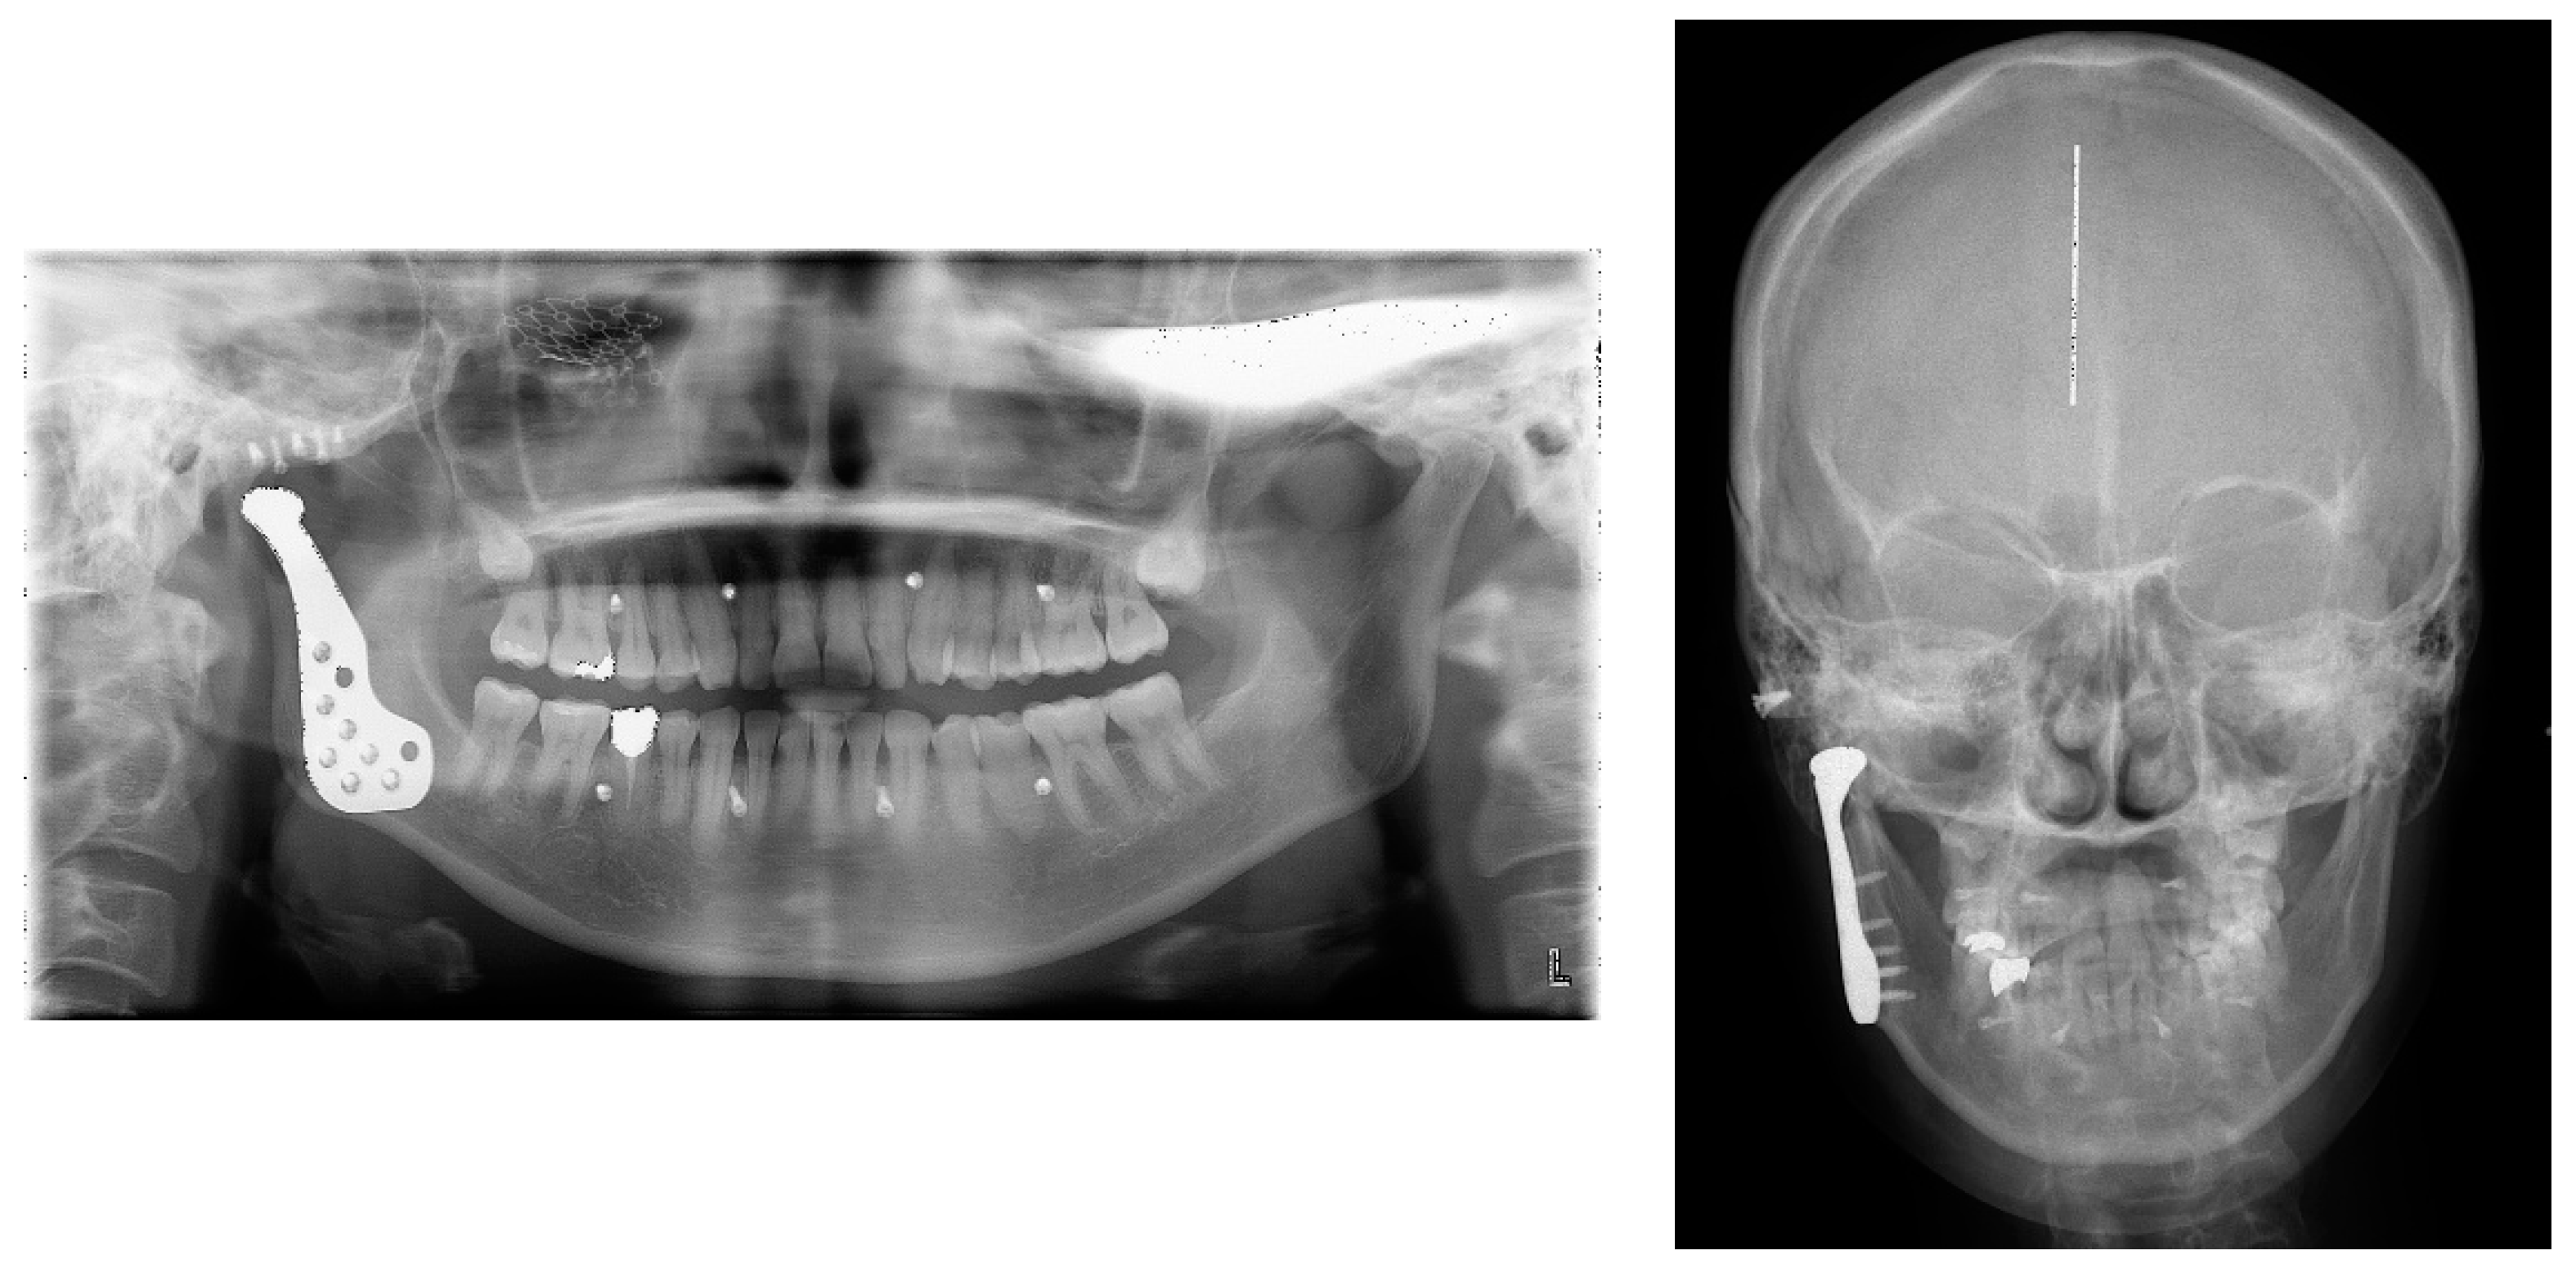

| Patient | Age | Gender | Operation Site | Diagnosis | Previous Treatment & Present Illness |

|---|---|---|---|---|---|

| 1 | 68 | M | Rt. | (1) Malunion of Rt. condyle (2) TMJ ankylosis & osteoarthritis | ORIF & mouth opening limitation |

| 2 | 80 | M | Rt. | Degenerative osteoarthritis severe anatomical changes of Rt. condyle | Severe erosion & bony ankylosis of condyle |

| 3 | 62 | M | Lt. | Comminuted fracture of Lt. condyle | Closed reduction |

| 4 | 44 | F | Rt. | TMJ ankylosis of Rt. condyle | Arthroplasty & Chronic pain |

| 5 | 52 | M | Rt. | (1) Osteochondroma of Rt. Condyle (2) Fracture of R-plate | Mass removal & reconstruction with rib bone and cartilage |

| 6 | 57 | M | Rt. | Comminuted fracture of Rt. condyle | Open bite & mouth opening limitation |

| 7 | 44 | F | Lt. | Comminuted fracture of Lt. condyle | ORIF & mouth opening limitation |

| 8 | 63 | F | Lt. | Osteoma with degenerative change of Lt. condyle | Biopsy (Osteoma) & malocclusion |